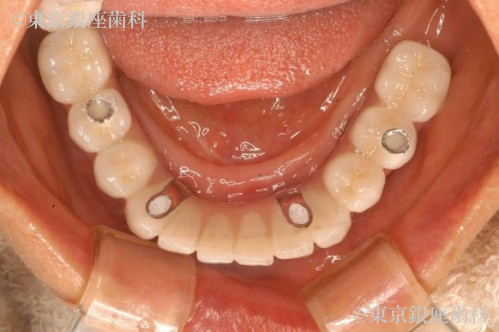

歯周病の進行により歯に動揺があり長期の保存が難しくこのままでは予後が不安であった為全顎的な治療が必要と判断。上下全ての歯を抜歯。重度の歯周病により骨が吸収されているため、上顎骨が薄く左側は上顎洞に骨を足す治療(サイナスリフト)を行い上顎に4本、下顎に4本のインプラントを埋入しワンデイインプラントを行った。現在半年メンテナンス。

抜歯即時埋入でインプラント治療を行い、その日のうちに仮歯を入れて短期間での大幅な審美、機能の回復をした。また上顎骨が薄くインプラント埋入の難しい部位には人口骨を足しインプラント埋入を可能にした。